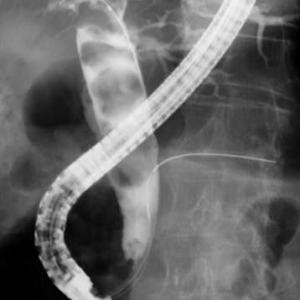

結石が胆管を閉塞し、胆管炎、閉塞性黄疸、急性膵炎などを発症します。緊急の処置が必要な場合が多く、放置すると命に係わる場合があります。通常バスケットカテーテルを用いて、結石を取り除きますが、石が大きい場合はESWL(体外衝撃波結石破砕術)を併用し排石する場合もあります。

ESWLとEST後large balloonによる乳頭拡張術を併用し完全排石に成功した巨大総胆管結石の一例